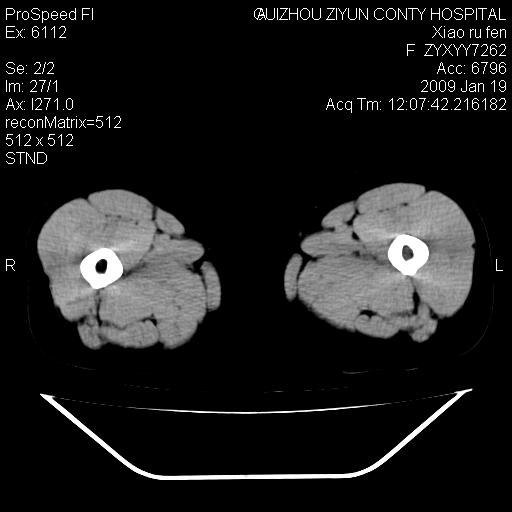

以下是引用zbp537在2009-1-19 14:25:00的发言:[br]考虑两个诊断:1、皮脂腺囊肿伴感染。2、脓肿。[br]诊断依据:[br]1、肿块为低密度,边界较清,和皮肤相连,周围结构清晰,未见受累及。[br]2、诊断脓肿是因为其内密度不均匀,当然要结合病史,因为脓肿临床上肯定表现为红肿热痛,也希望楼主把病史提供全面些,这些便于讨论。

以下是引用随光逐影在2009-1-19 16:15:00的发言:[br]左侧臀部类似软组织密度肿块,性质待定(不排除肿瘤可能);建议行进一步检查。